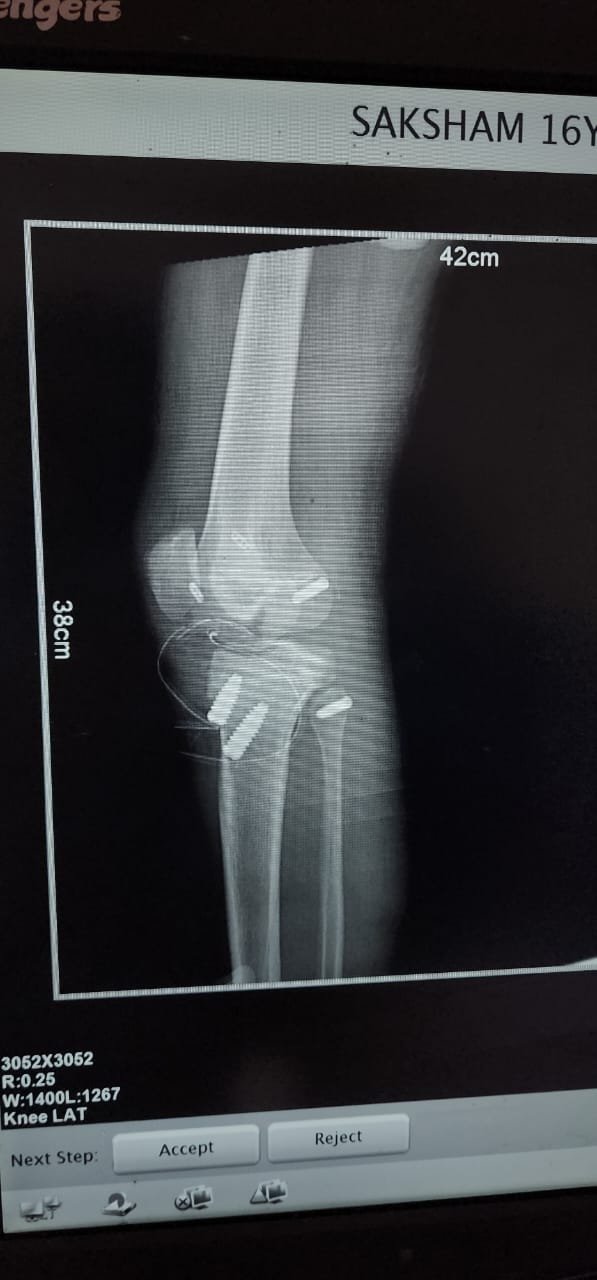

- ACL Reconstruction

- PCL Reconstruction

- Arthroscopy-Knee

- Fracture Treatment